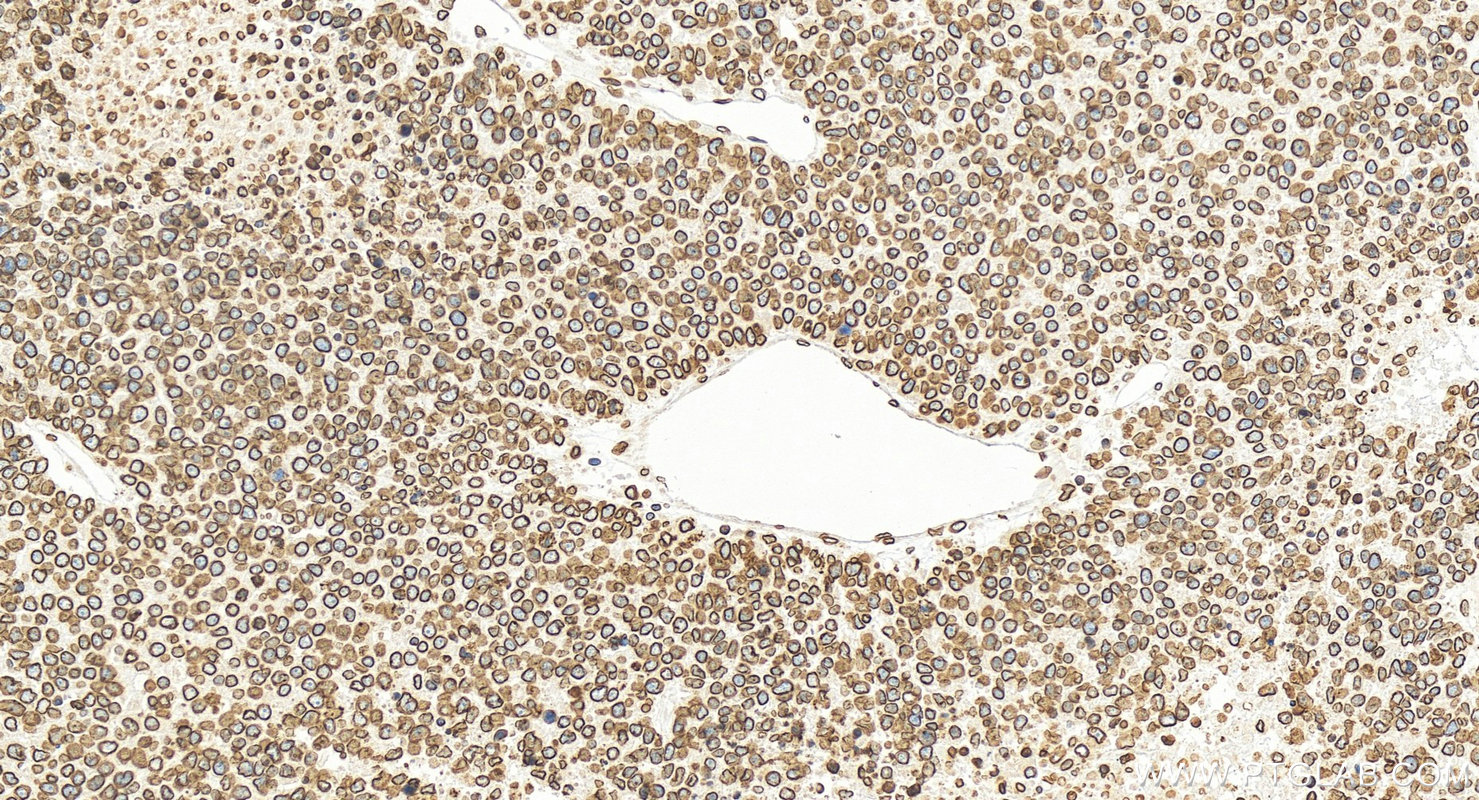

| Positive IHC detected in | mouse heart tissue, human colon tissue, human colon cancer tissue, human hepatocellular carcinoma, mouse kidney tissue Note: suggested antigen retrieval with TE buffer pH 9.0; (*) Alternatively, antigen retrieval may be performed with citrate buffer pH 6.0 |

| Immunohistochemistry (IHC) | IHC : 1:1000-1:4000 |